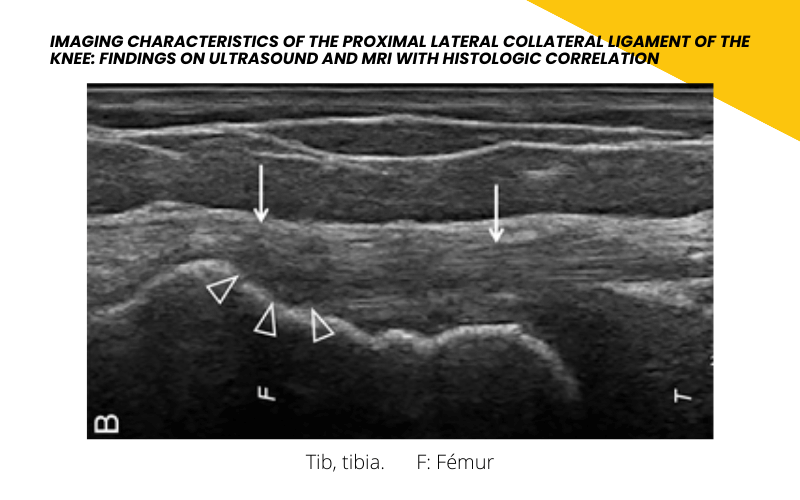

La ecografía muestra un ligamento colateral lateral hiperecoico homogéneo (flechas) en el sitio de inserción proximal.

La imagen de ultrasonido muestra un área hipoecoica (puntas de flecha) en el sitio de inserción proximal del ligamento colateral lateral (flechas).